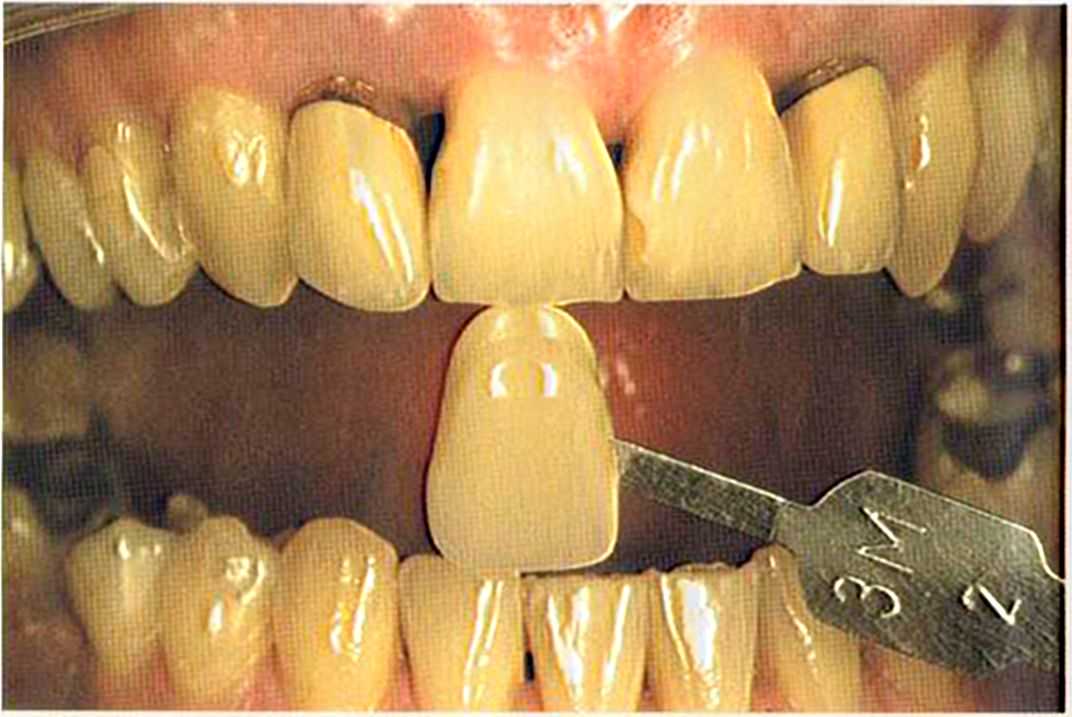

После того как мы определит цвет зуба, решено быо сначсьа изготовить одну коронку.

Цвет 1М1 до 1М2 основной цвет в данном случае.